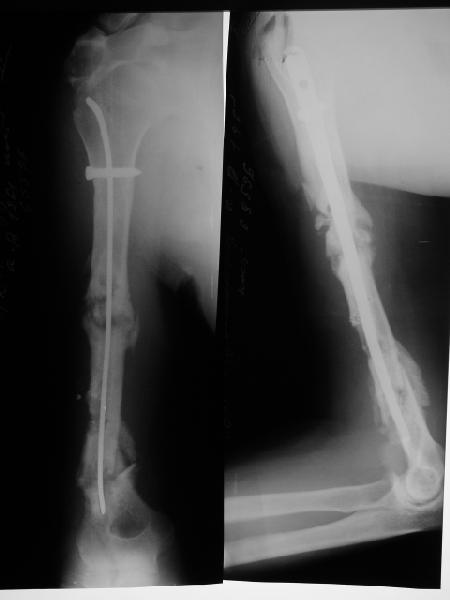

Такие надмыщелковые переломы в изолированном виде у нас в последние годы обычно фиксируются плоским титановым стержнем a la Зверев-Ключевский антеградно. Но тут еще и вышележащие проблемы.

Наверно, можно пойти на укорочение, убрав металлический цилиндр, не такой уж большой дефект. Снимки в чем-то похожего пациента прилагаю - тоже несращение диафиза после многократных операций, и надмыщелковый свежий перелом (случился после удаления обломка стержня аппарата).

Конечно, пьянство с падениями и прочими упражнениями ставит под вопрос любое дальнейшее лечение. Аппарат, что ли, еще и поверх наложить... В качестве внешнего металличкеского каркаса...